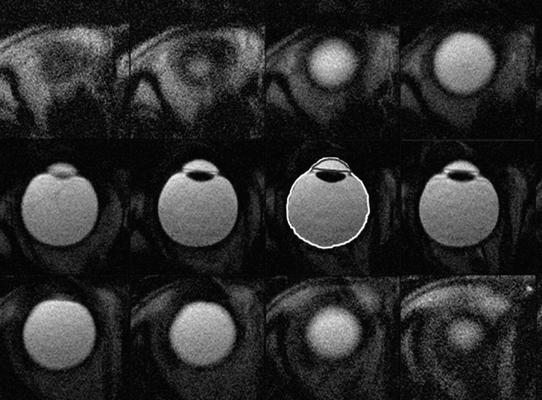

Во время обследования рекомендуется зафиксировать взгляд, и до его завершения стараться смотреть в эту точку (в том числе и при закрытых глазах). В процессе исследования делаются мелкие компьютерные «срезы» орбиты и ее структур в трех проекциях. Продолжительность процедуры составляет 10-12 минут. Если она дополняется контрастным усилением, время немного увеличивается.